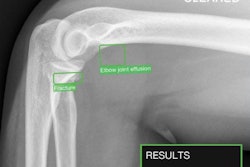

A representative posteroanterior chest x-ray (A) in a 71-year-old male patient who underwent examination due to progression of dyspnea shows bilateral fibrosis (arrows), which was misclassified as airspace disease by all four AI tools. Image courtesy of Radiology.